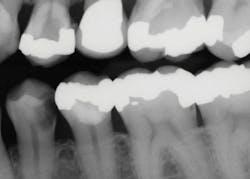

Use the following technique to remove deep caries for indirect restorations, such as crowns and onlays (figures 2–4):

Figure 2: This patient requires significant treatment. The second premolar was extracted, and the other three teeth received caries excavation and treatment as described in this article.